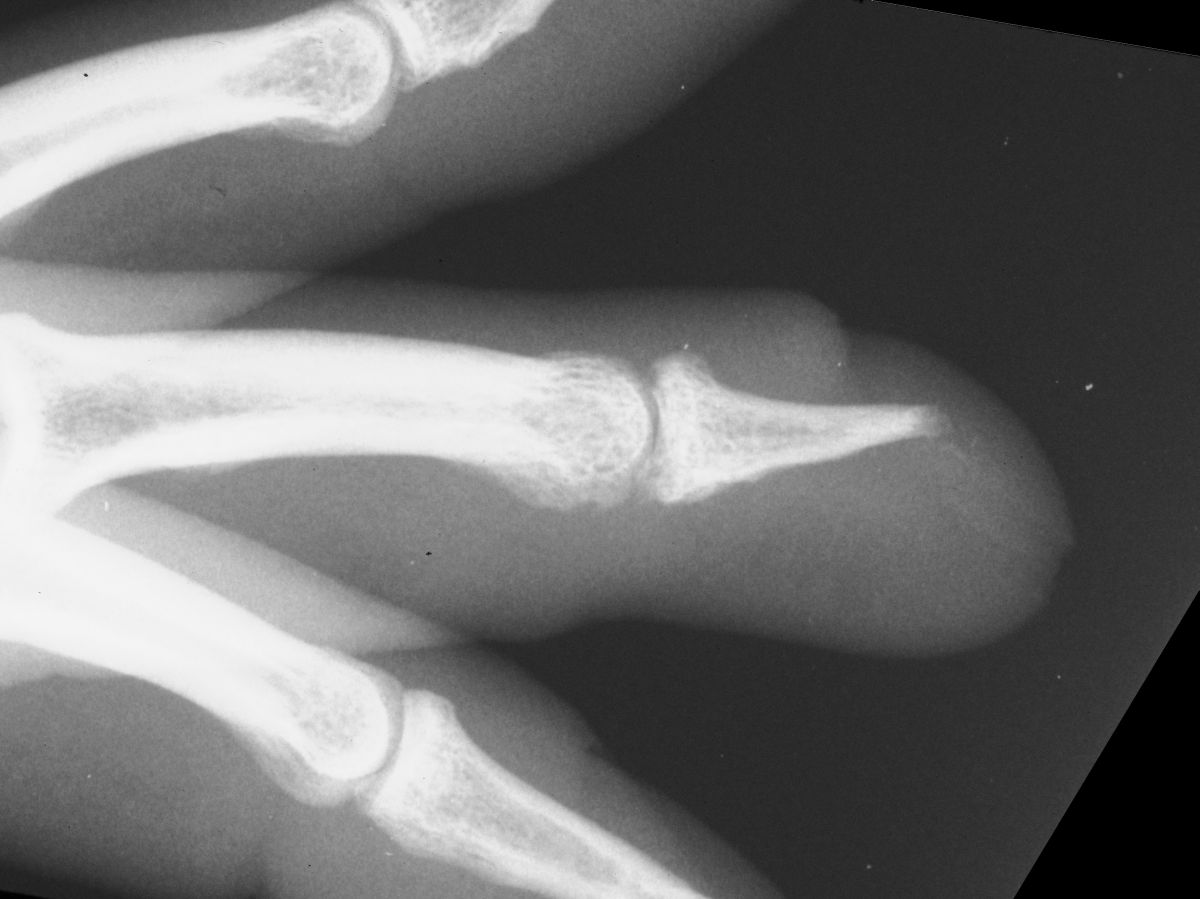

| Case

4. A dog bit off this young man's index fingertip. Although the PA Xray looks as though the bone was kept, additional views show an amputation through the tuft. |

| The defect. |